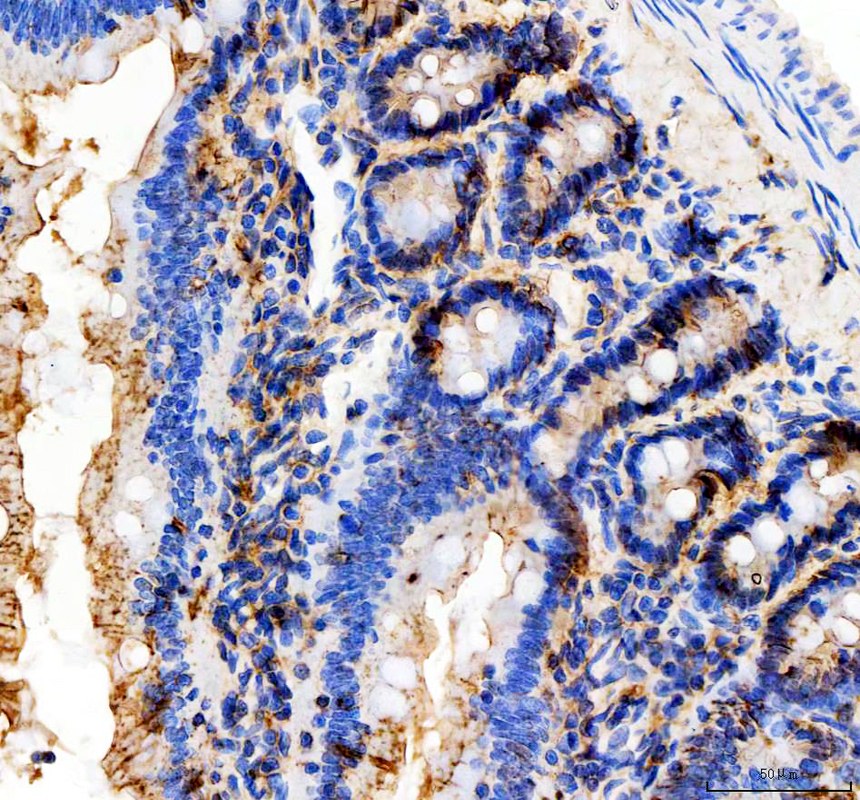

IHC analysis of E-cadherin/CDH1 using anti-E-cadherin/CDH1 antibody (PB9561).

E-cadherin/CDH1 was detected in a paraffin-embedded section of rat colon tissue. The tissue section was incubated with rabbit anti-E-cadherin/CDH1 Antibody (PB9561) at a dilution of 1:200 and developed using HRP Conjugated Rabbit IgG Super Vision Assay Kit (Catalog # SV0002) with DAB (Catalog # AR1027) as the chromogen.